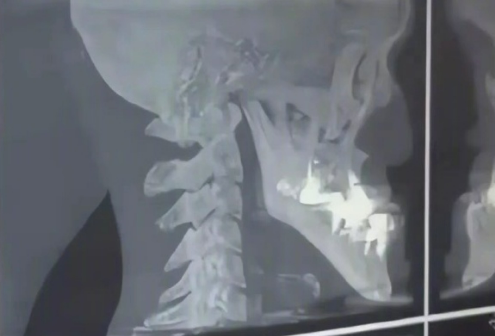

随后,有医生推测可能是摄入过多牛奶导致下颌骨或牙龈异常生长,建议他前往牙科进行X光检查。

检查结果表明,他的骨骼和牙齿结构完全正常,只是下巴在自然发育过程中异常增长。

通常情况下,普通人的下巴长度约为3厘米,而这位男子的下巴正面测量达5厘米,侧面更是达到11.5厘米,成为目前有公开记录以来自然生长的最长下巴保持者。